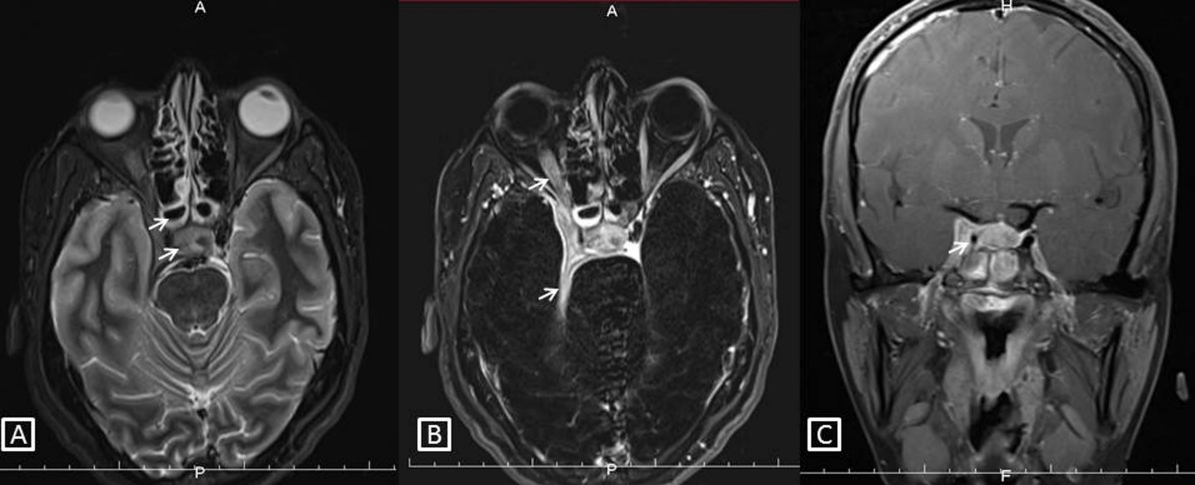

Magnetic resonance imaging (MRI) was advised and mucosal thickening was noted in both compartments of the sphenoid sinus. Areas of altered bone marrow signal intensity with adjacent bone destruction were observed involving the walls of the sphenoid sinus (Figure 1A [Fig. 1]), bilateral posterior clenoid processes, right anterior clenoid process, dorsum sella, the proximal half of clivus, and the right petrous apex region. Posterior one third of the intraorbital portion and of the intracanalicular portion of the right optic nerve, the right half of the optic chiasm was enlarged and showed hyperintense signal intensity on subtracted post contrast T1 image (Figure 1B [Fig. 1]). A hyperintense signal was also noted involving the right optic tract. We also observed a mild enlargement of the pituitary gland and pituitary stalk. Post contrast T1 image in the coronal plane showed an asymmetry of the right cavernous sinus due to enhancing soft tissue within it. (Figure 1C [Fig. 1]). These imaging features were suggestive of fungal sphenoid sinusitis with osteomyelitis involving the right cavernous sinus, adjacent dura, right optic nerve pathway, and pituitary gland.

Figure 1: Sphenoidal sinus osteomyelitis.

A) Fat suppressed T2 image in the axial plane showing sphenoid sinusitis, altered signal intensity in adjacent bones with expansion of right cavernous sinus by soft tissue (white arrows). B) Subtracted post contrast T1 image in the axial plane showing enhancing soft tissue thickening in the right cavernous sinus with extension to the orbital apex. There is an enhancement of the adjacent right optic nerve and the right half of the optic chiasma shows abnormal signal intensity (white arrows). C) Post contrast T1 image in the coronal plane shows a striking asymmetry of the right cavernous sinus due to enhancing soft tissue within it. Note the narrowed caliber of the cavernous segment of the right internal carotid artery compared to the left (white arrow).